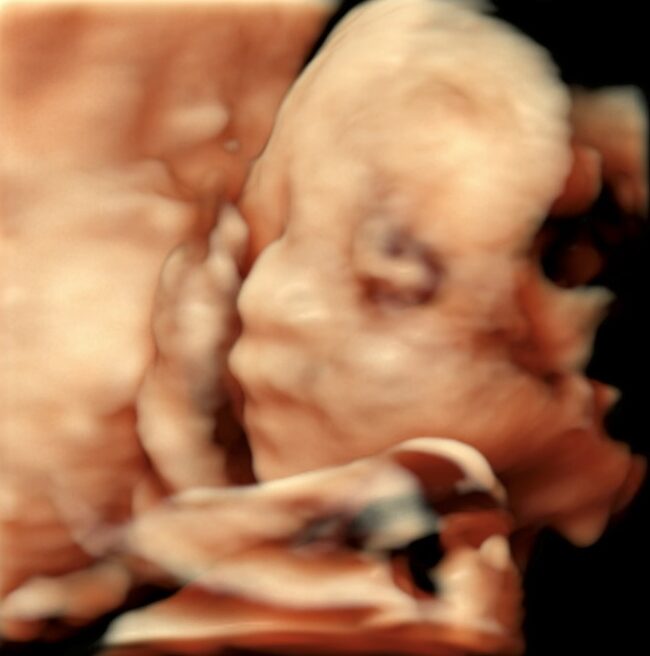

条件が良ければ、こんな感じで赤ちゃんをみることができます(写真は、お母さんにホームページに載せることを許可していただいています)。

赤ちゃんの協力も必要なので、残念ながらいつもこのようにみえるわけではありまんが、

お腹の中で元気に育っている姿をみると、幸せのおすそ分けをしてもらっているような気分になります。

一番はじめのエコー画像は妊娠9週のものですが、この時期ですでに頭も手も足もしっかりできています。